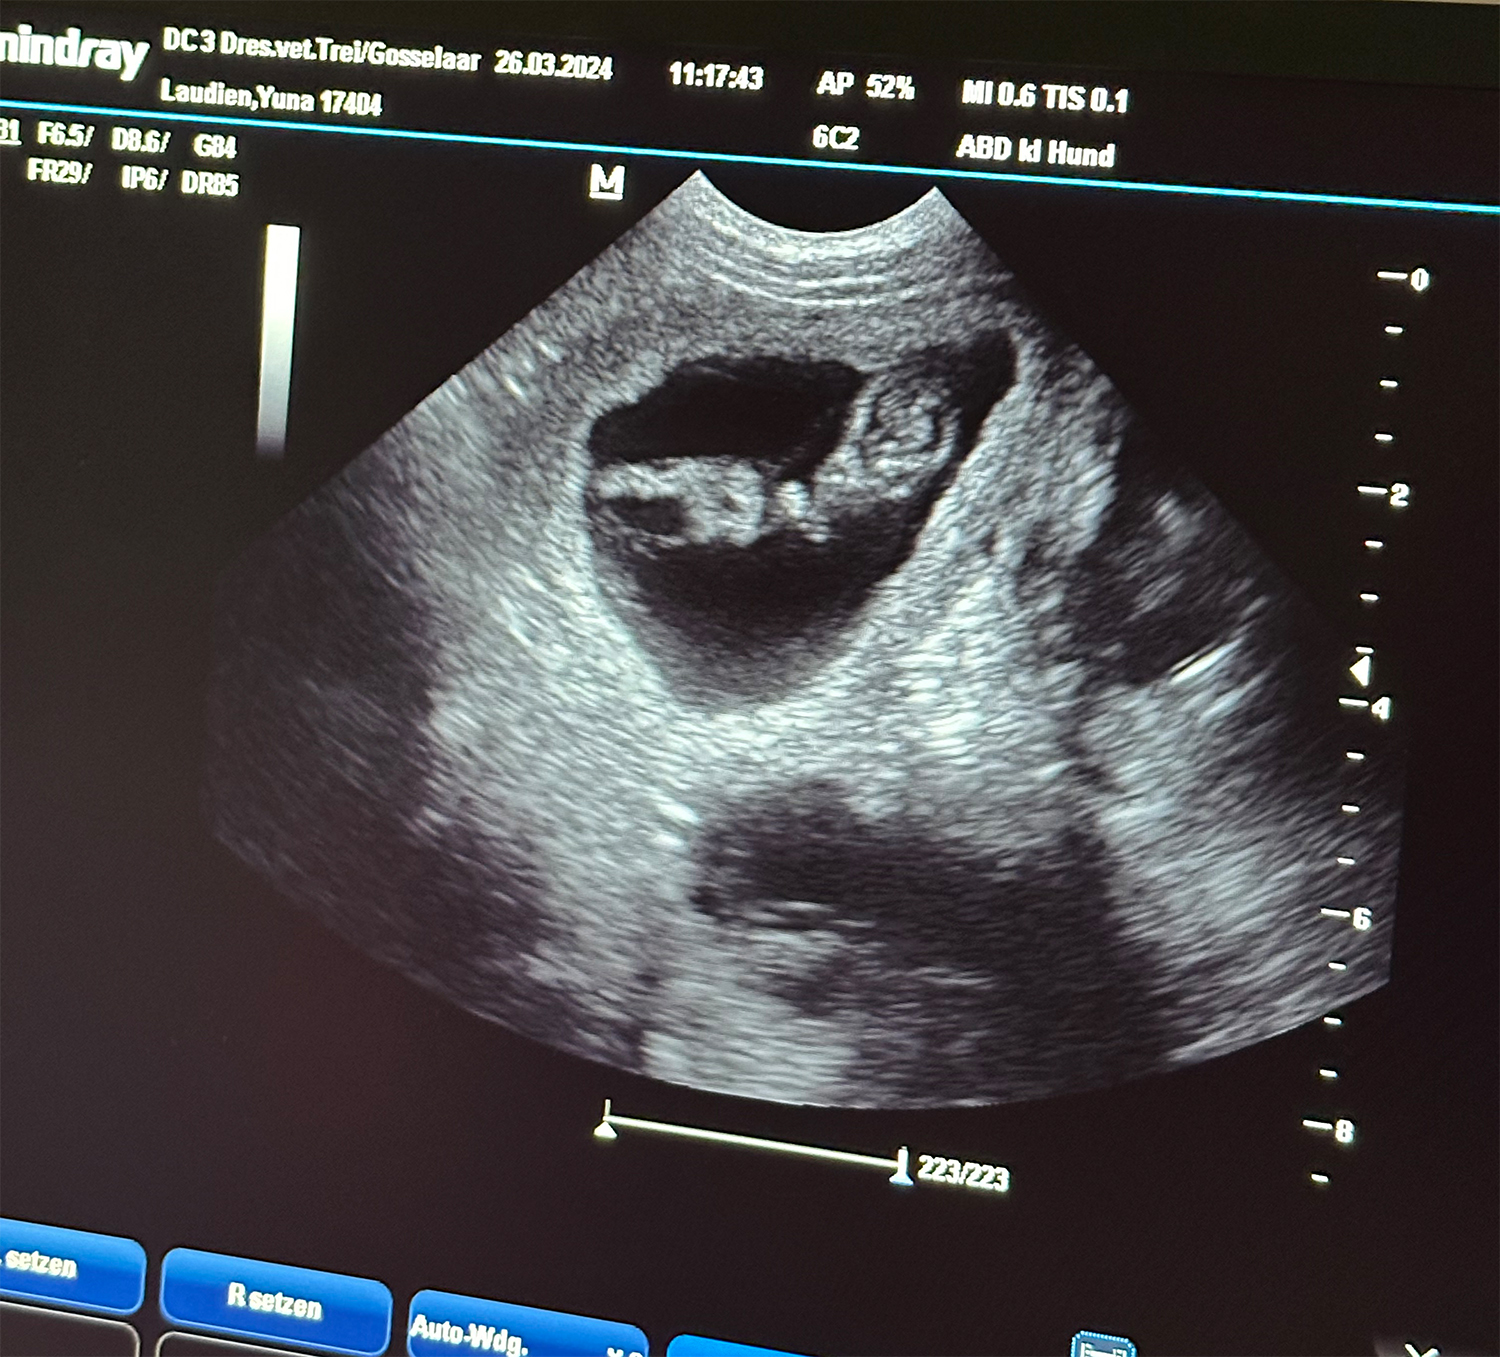

Heute war also der Tag der Tage. Der Tag an dem man Gewissheit bekommt, ob die Hündin aufgenommen hat oder nicht.

Auch wenn in den letzten Tagen einiges für eine Trächtigkeit gesprochen hat, so wollten wir es gerne

von unserer Tierärztin Insa Gosselaar absegnen lassen.

Beim Ultraschall wurden auf Anhieb einige Fruchtanlagen gesichtet. Die genaue Anzahl wollte ich aber nicht wissen.... ein bisschen Spannung soll uns und den Welpeninteressenten schon noch in den kommenden Wochen erhalten bleiben.  |

Wir freuen uns einfach riesig darüber, dass bald kleine L-Racker den Bagalutenhof besetzen werden.

Bis dato werden wir Yuna fit halten und gut auf unser Essen aufpassen. |